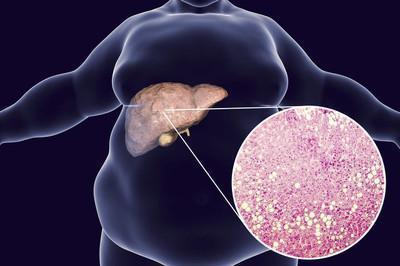

高血脂危害大,会伤害身体三大器官!1、导致脂肪肝血液滋养着身体的各个器官,肝脏也不例外,当血脂高时,很容易诱发脂肪肝,影响肝脏的健康。这样,人体解毒自然也会受到影响,并会出现一系列肝功能异常的症状。患者会出现皮肤发黑、厌食、恶心的症状,以及还会出现肝区严重疼痛的症状。